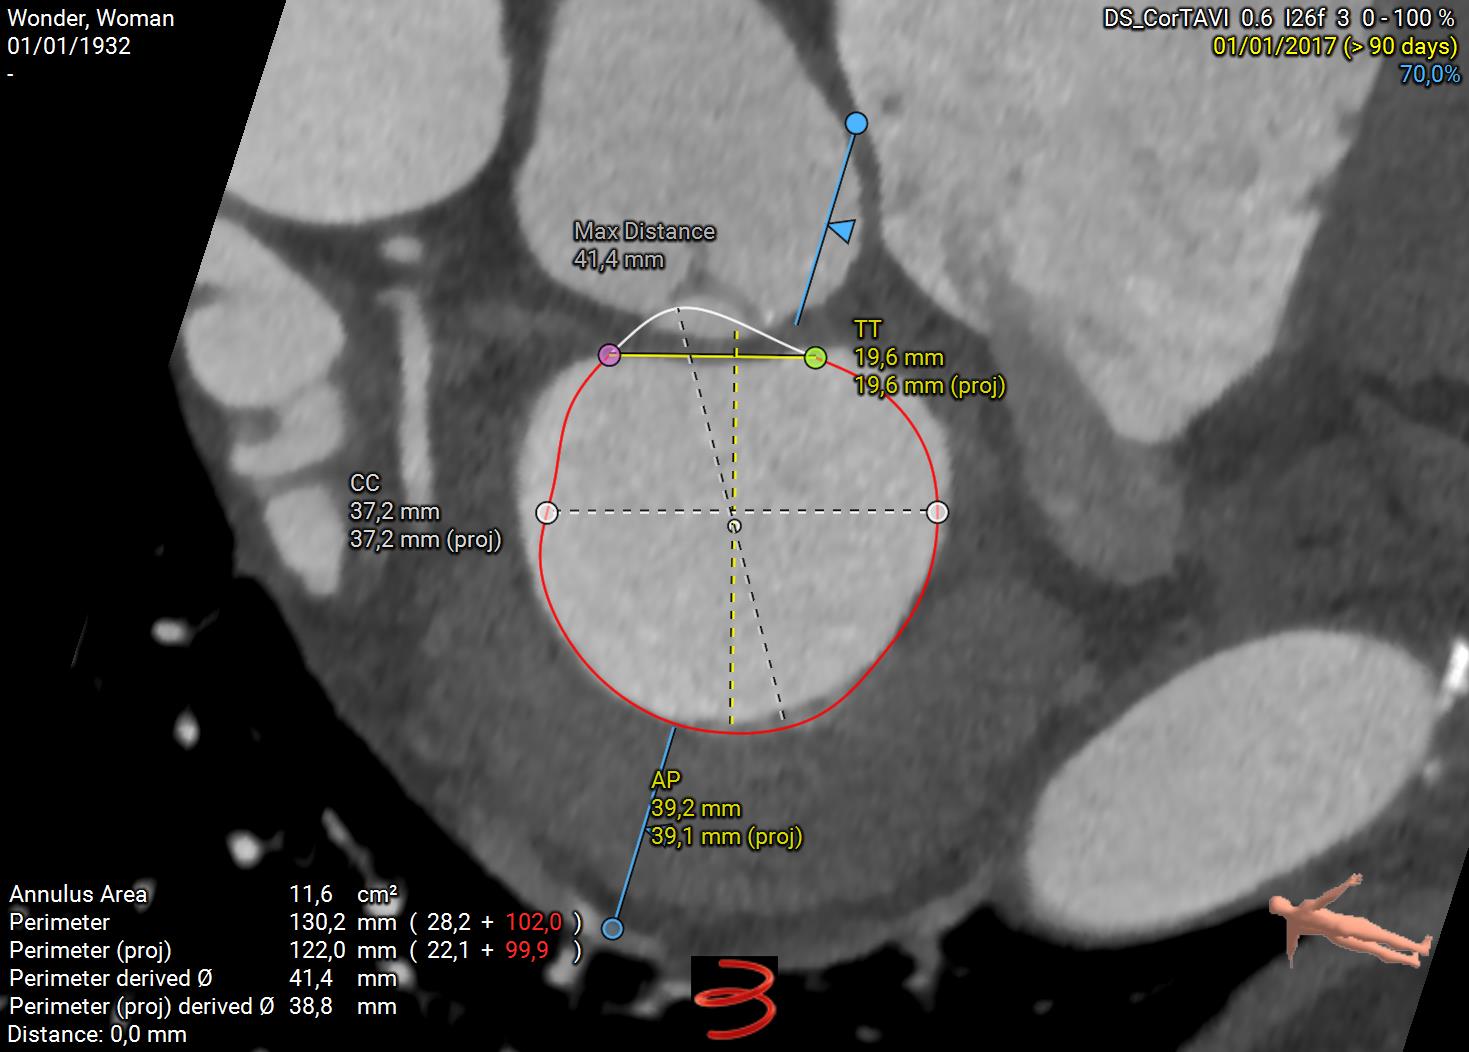

Role of Imaging in TMVR Planning

Advanced imaging is essential to assess anatomy and ensure a safe procedure:

1. Cardiac CT:

• Measures mitral annulus size

• Evaluates neo-LVOT area to prevent outflow obstruction

• Identifies calcium distribution

Planning TMVR with 3mensio Software

3mensio Structural Heart streamlines TMVR planning by offering:

• Accurate annular sizing

• Neo-LVOT area prediction

• Assessment of annular and sub-annular calcification

• Simulation of transapical or transseptal access paths

This enables precise device selection, positioning, and risk management—especially in anatomically complex cases.